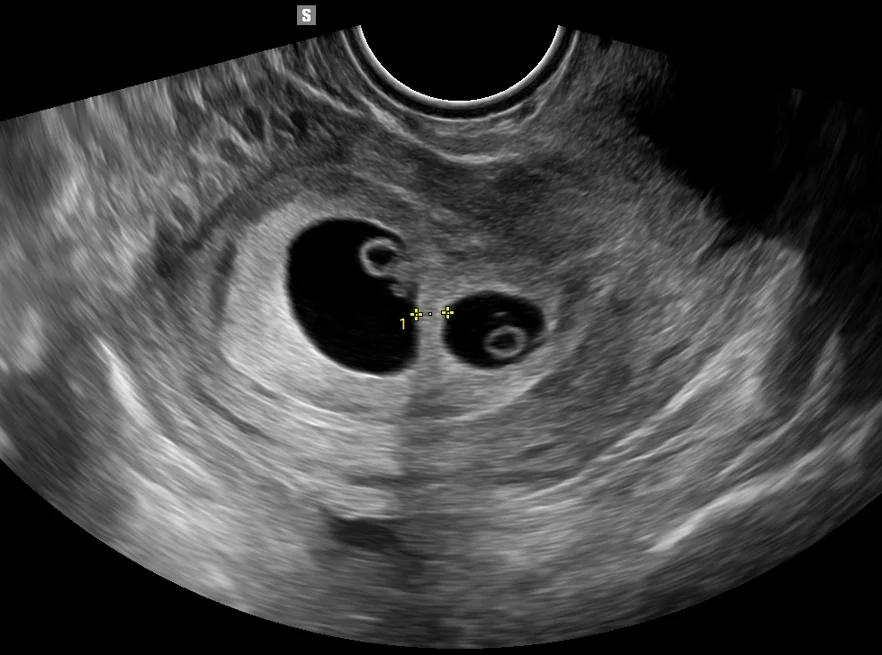

Early Ultrasound for Dating (6–10 weeks)

• Confirms pregnancy viability

• Determines gestational age

• Detects early concerns like subchorionic bleed, twins, etc.

Transvaginal Sonography (TVS)

High-resolution imaging for early pregnancy, placental location, cervix length, previa, and targeted evaluations.